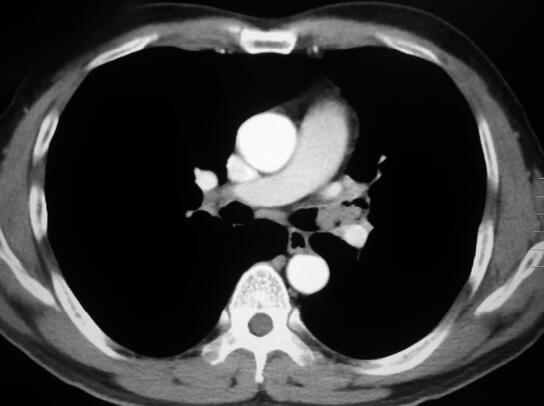

4.胸部增强CT:

左主支气管内见结节样肿物阻塞管腔,病灶强化不明显,局部低密度灶(图1)。

图1